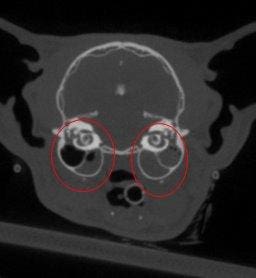

This cat has middle ear disease, another problem that would not have been found with dental radiographs.